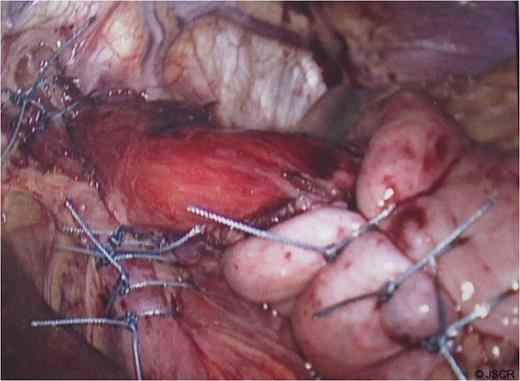

At operation, a large hiatal defect of 5cm and a moderate size sac was found (Fig 1) that was mobilised and adhesions divided to obtain 3cm of oesophageal length in the abdomen. Following division of the upper short gastric vessels, a posterior hiatal repair with seven interrupted ethibond stitches and a loose 360 degree full wrap with the fundus of the stomach with three interrupted ethibond stitches were performed. Wrap was further fixed to the diaphragm and right crus with another three ethibond stitches (Fig. 2).

Hiatus hernia with portion of stomach seen going into the chest